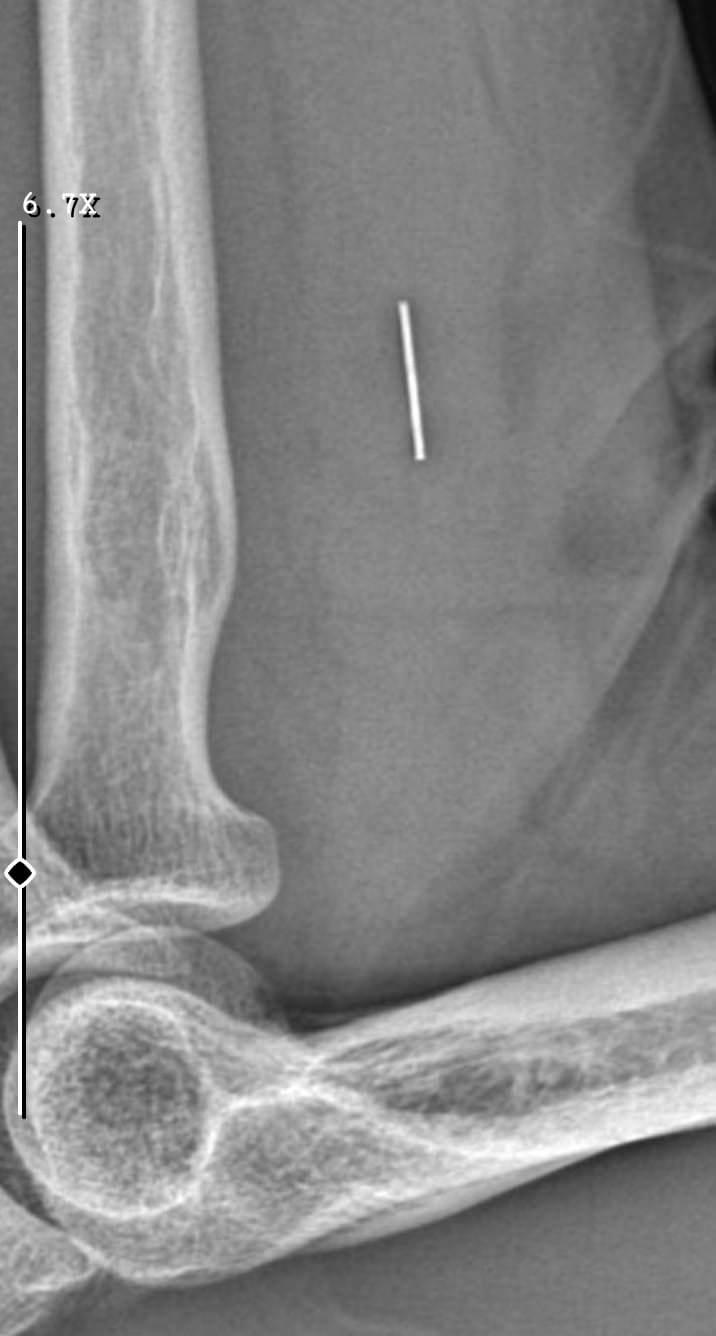

Öte yandan, ameliyatların ardından ağrıları devam eden Güleryüz'ün kolunda metal parça bulunduğu ve bu parçanın parmak bölgesinden dirseğe doğru ilerlediği öne sürüldü.

"Doktorlara bileğime doğru ağrılarım olduğunu sürekli ifade etmeme rağmen beni dinlemediler. Sonradan kolumda metal kaldığını öğrendik. Bunun ihmal olduğunu düşünüyoruz. Çünkü kola metal nasıl girebilir? Ben 9 aydır çalışamıyorum. Kalp rahatsızlığım sebebiyle yüzde 46 engelliyken şu anda yüzde 75 engelli durumuna düştüm. Erken emeklilik dilekçesi verdim ancak henüz sonuç gelmedi. Bu konuda çok mağdurum. Yetkililerin bunu duymasını istiyorum. Savcılığa suç duyurusunda bulunduk. Yaklaşık 9 aydır henüz soruşturma izni gelmedi. Süreci bekliyoruz, henüz dava açılmış değil. Kolumda bırakılan metal ilerliyor. Pazartesi günü bunun için de operasyon geçireceğim. Çıkarılıp çıkarılamayacağı net değil. Elimde titremelerim var, çalışamıyorum ve işveren tarafından işten çıkarıldım. Yetkililerden destek ve konunun incelenmesini talep ediyorum."